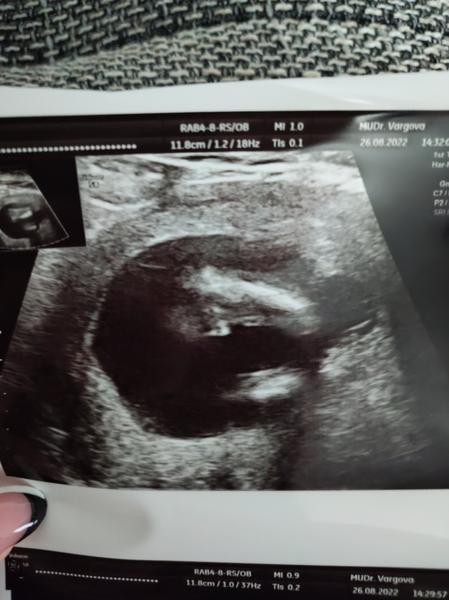

@zuzsat tak u mna uz potvrdene tehotenstvo ❤️❤️❤️❤️❤️ Aj srdiecko uz bije

@katyk22 ja som bola vcera u sukromnika lebo kija ˇi dala termin az 28.9. Co je 9+4tt

Vcera som bola 6+5tt a vidiet j mimi aj srdiecko bilo

@aurora1992 9+4 sa mi zdá riadne neskoro. Ideál je 7 týždňov. Tak hneď si spokojnejšia však?? Gratulujem a držím palce aby bolo naďalej všetko ok. 😊

@adela232 ani nevrav, na nervy som z toho bola ale tak za 30€ viem, ze je vsetko v poriadku 🙂 a mozem to oznamit zamestnavatelovi